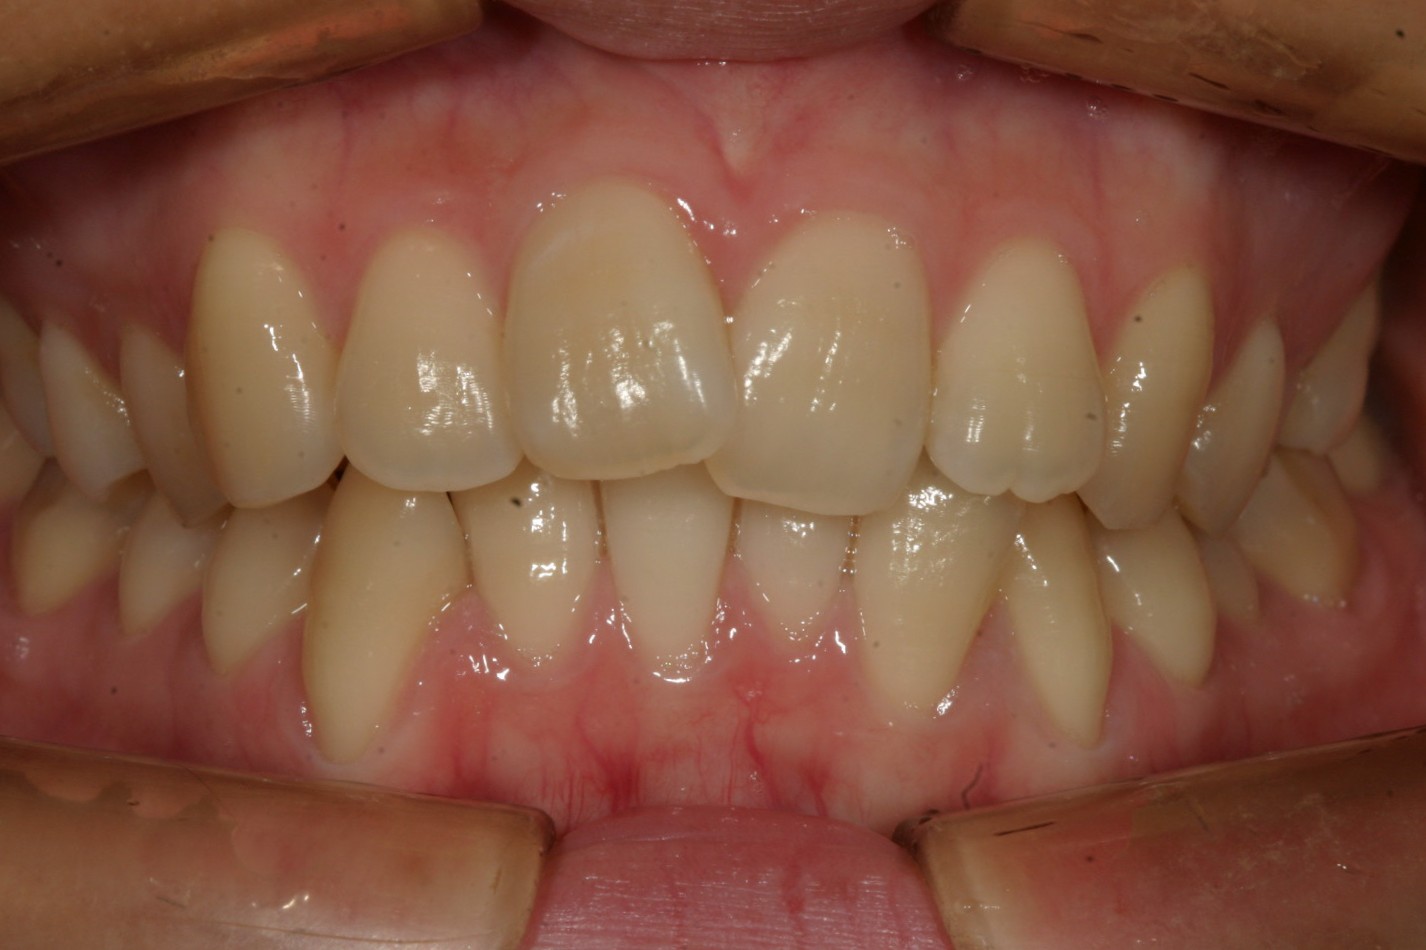

上の前歯が出てるのと下の前歯のガタガタ

一歯だけ飛び出てるのが気になります。

側面観はちょい出っ歯です。

こちらの症例は典型的な症例で歯列形が悪い為の不正咬合です。